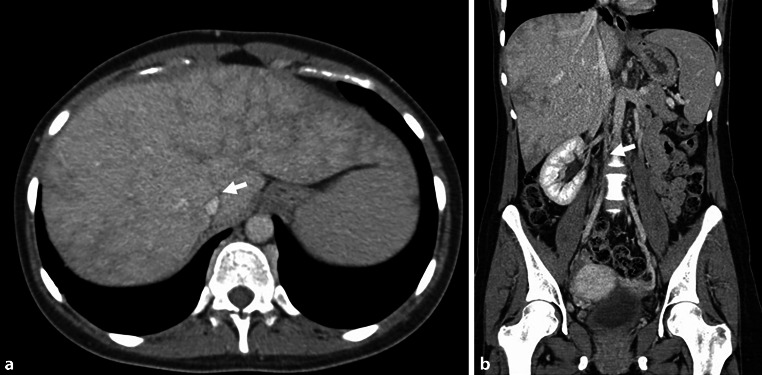

After one more severe episode of hemoptysis 3 weeks after initial presentation, the patient underwent another CT examination, which revealed progression of the diameter of the aneurysms of the main pulmonary arteries (Fig. 2a–d) and multiple patchy ground-glass opacites, compatible with a pulmonary hemorrhage. Abdominal CT showed a complete obliteration of the inferior vena cava due to thrombus and fibrotic changes over the entire length. The liver showed parenchymal perfusion abnormalities and thrombosis of the left and middle hepatic vein consistent with Budd-Chiari syndrome (Fig. 3).

Fig. 3.

a The axial CT scan of the abdomen shows the Budd-Chiari syndrome with a thrombosis of the middle and left hepatic veins (arrow). b Coronal reformation of the CT shows a fibrotic occlusion of the inferior vena cava (arrow)